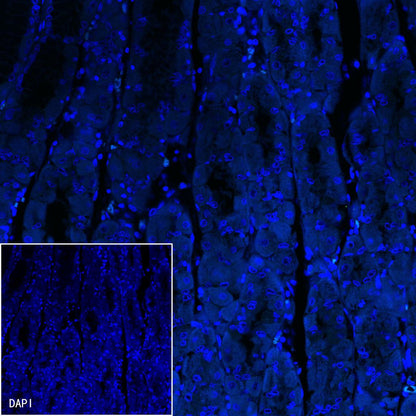

Immunofluorescence

IF shows positive staining in paraffin-embedded human stomach Hp(+). Anti-Helicobacter pylori antibody was used at 1/100 dilution (Green) and incubated overnight at 4°C. Goat polyclonal Antibody to Rabbit IgG - H&L (Alexa Fluor® 488) was used as secondary antibody at 1/1000 dilution. Counterstained with DAPI (Blue). Heat mediated antigen retrieval with EDTA buffer pH9.0 was performed before commencing with IF staining protocol.

Negaive control: IF shows negative staining in paraffin-embedded human stomach (Hp-). Anti-Helicobacter pylori antibody was used at 1/100 dilution and incubated overnight at 4°C. Goat polyclonal Antibody to Rabbit IgG - H&L (Alexa Fluor® 488) was used as secondary antibody at 1/1000 dilution. Counterstained with DAPI (Blue). Heat mediated antigen retrieval with EDTA buffer pH9.0 was performed before commencing with IF staining protocol.